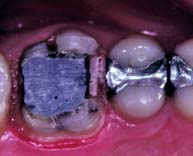

Bonding agents can assist amalgam retention, but adhesion is not adequate to resist occlusal loading. Retention is currently best provided by conventional means. An example of the use of bonding agents appears in Figure 6-8. If bonding agents are used, the clinician should follow the manufacturer’s directions about storage and manipulation.

Fig. 6-8 Adhesives such as AmalgamBond, a 4-methacryloxyethyl trimellitate anhydride (4-META) product, may be helpful in retaining amalgam foundations. A, Mandibular molar with extensive tooth structure loss prepared for foundation restoration. B, The dentin conditioner (10% citric acid, 3% ferric chloride) is applied in accordance with the manufacturer’s instructions. Then it is rinsed and lightly dried. C, The conditioner is primed, and the operator waits for 20 seconds. If puddles remain, the operator blows to eliminate them. It is not necessary to dry the primer. D to F, The adhesive is mixed, and the powder liner is incorporated and brushed into the prepared cavity. G, The amalgam is condensed while the liner is still wet. H, The finished restoration.

(Courtesy of Parkell Products, Inc., Farmingdale, New York.)